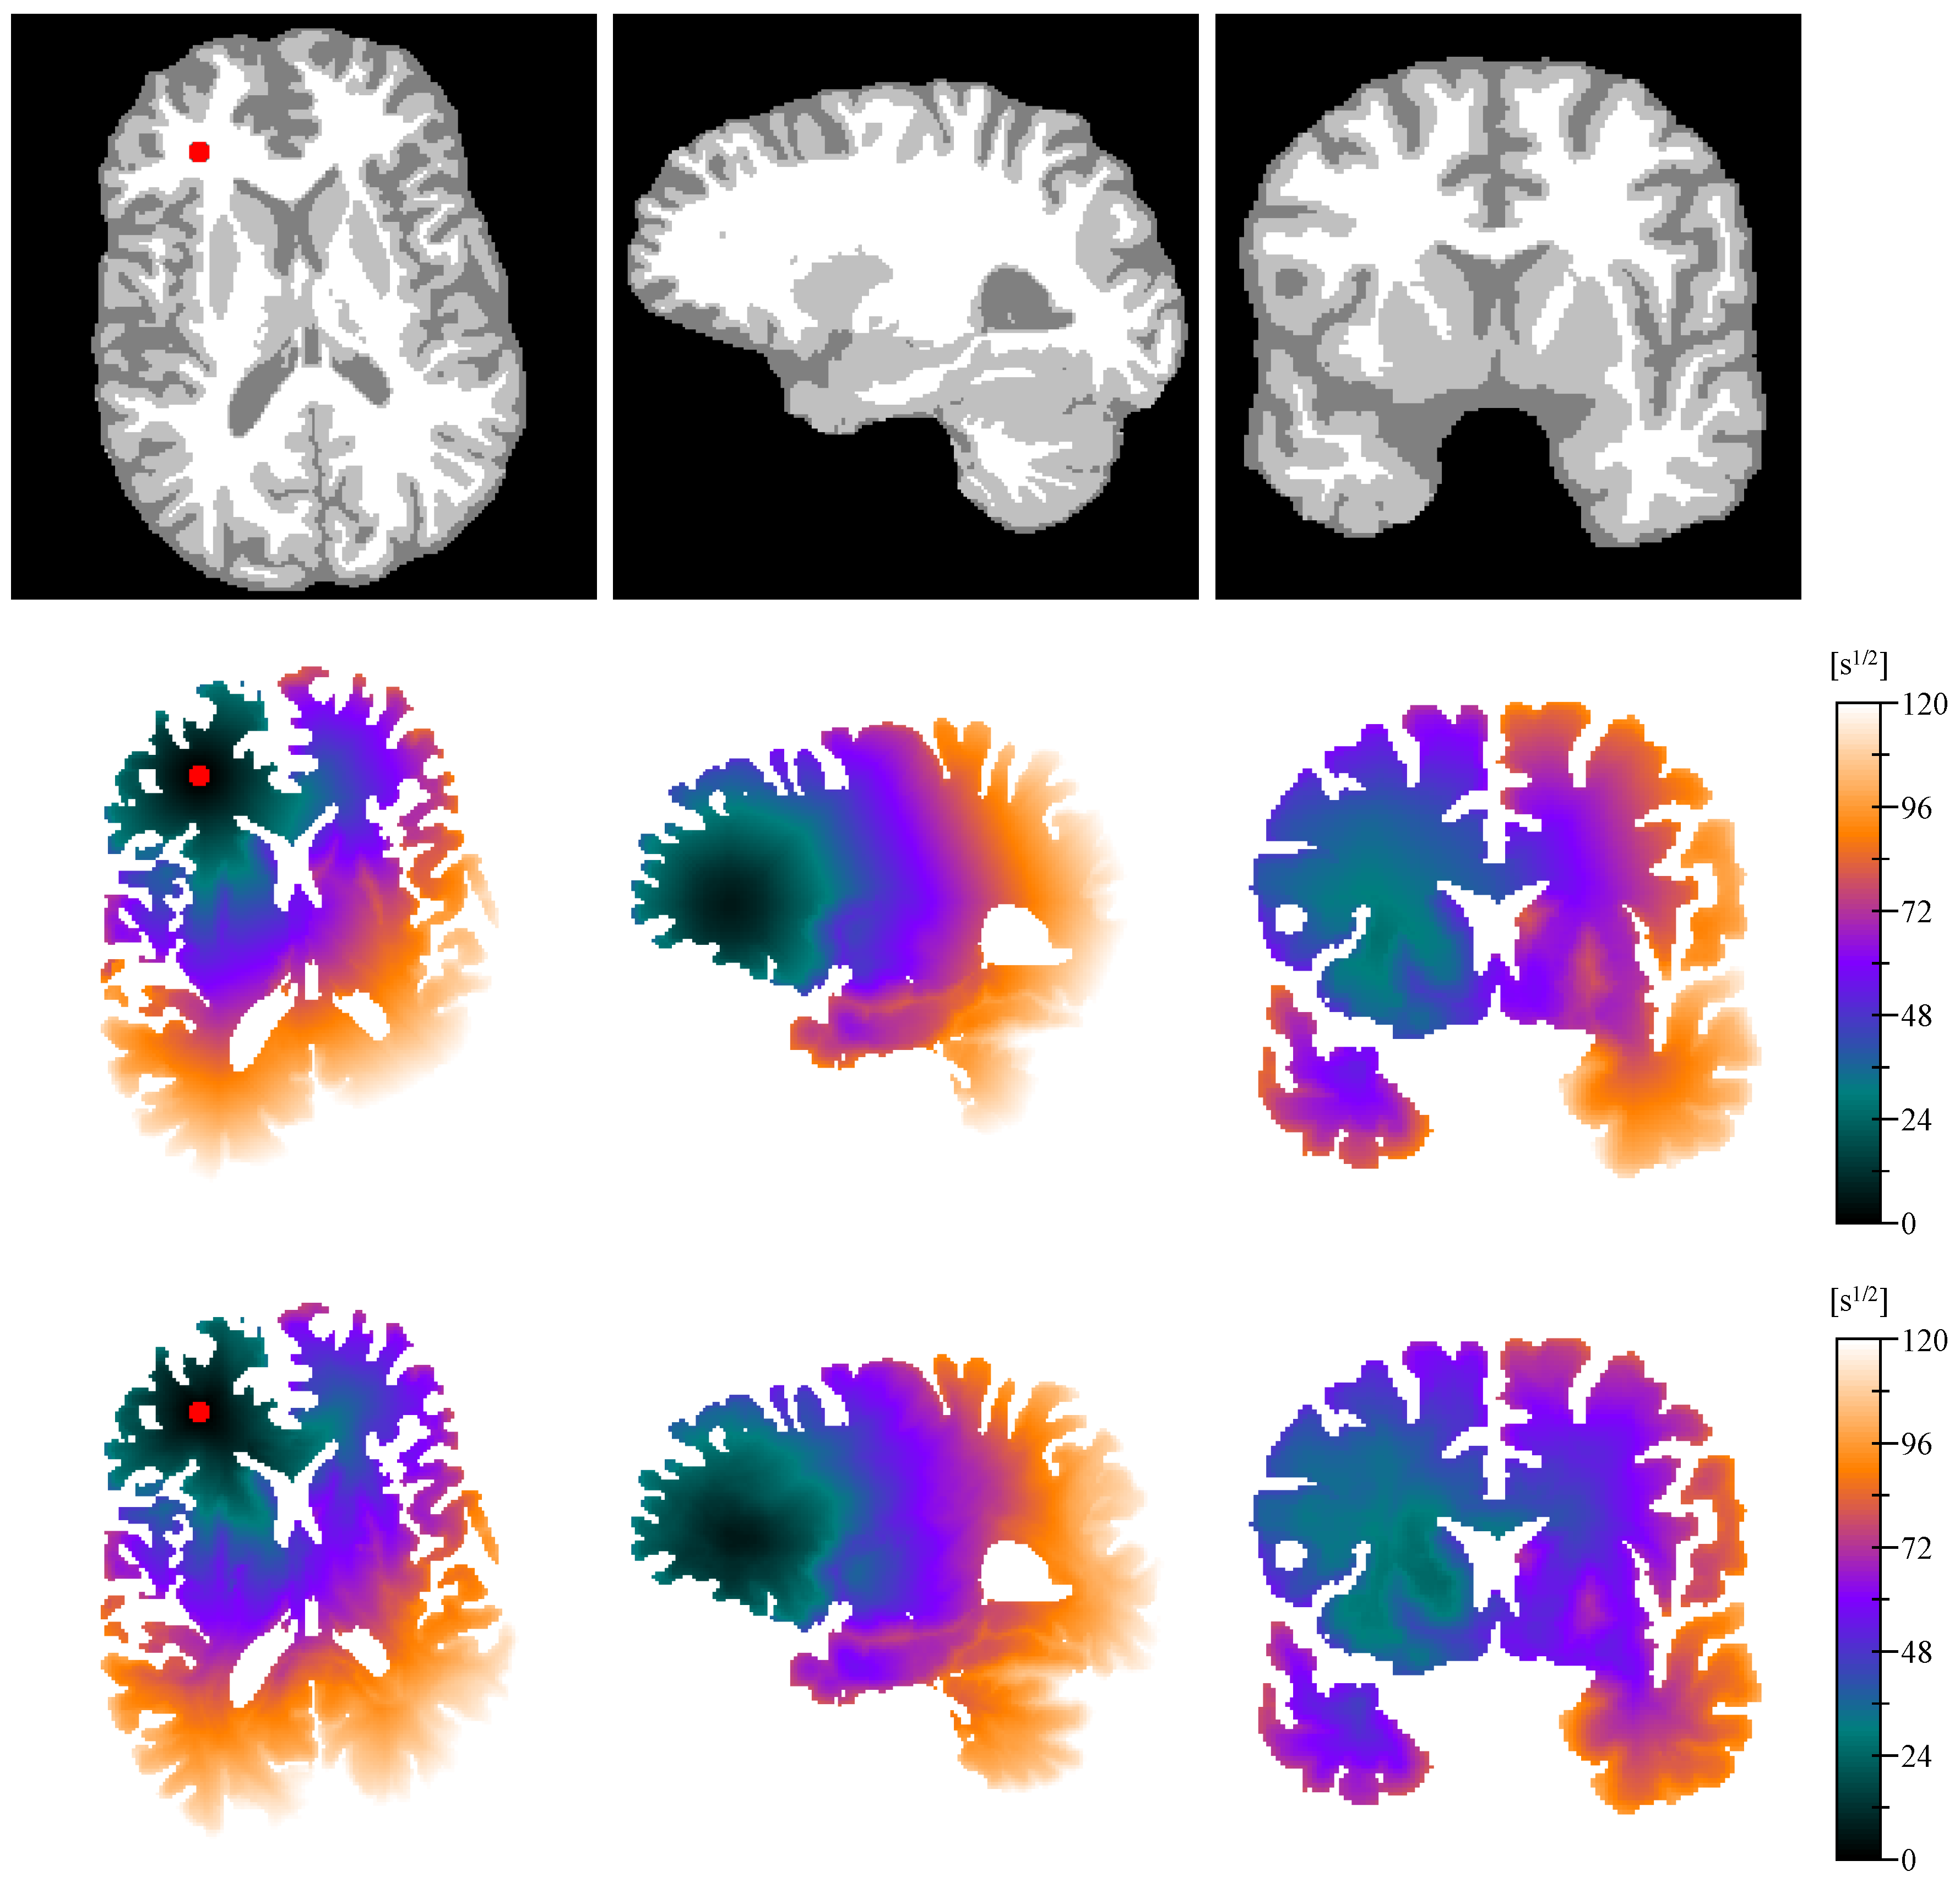

2.8. Distance Map

Appendix E. Isotropic vs. Anisotropic Metric Tensor